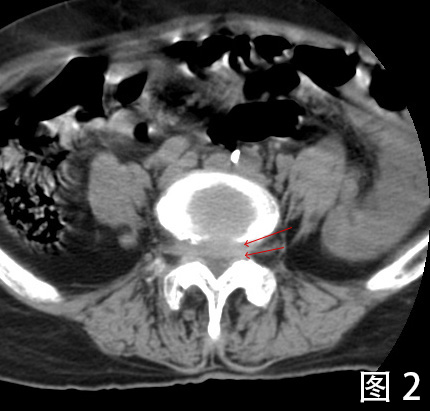

专科检查:2022-08-17 腰椎CT平扫检查阅片:腰椎椎体序列不稳定,椎管内可见增生钙化,继发椎管骨性狭窄。根据Meyerding分级, L4椎体向前I度滑脱,L5椎体向前II度滑脱,为连续2个节段的退行性滑脱(图1)。L3/4、L4/5、L5/S1椎间盘膨出,硬膜囊受压。L4、L5椎体小关节增生硬化明显,相应节段竖脊肌萎缩。椎间盘于相邻椎体层面以相反方向超出椎体边缘“夹心征”(图2)。L5椎体假关节形成(图3)。